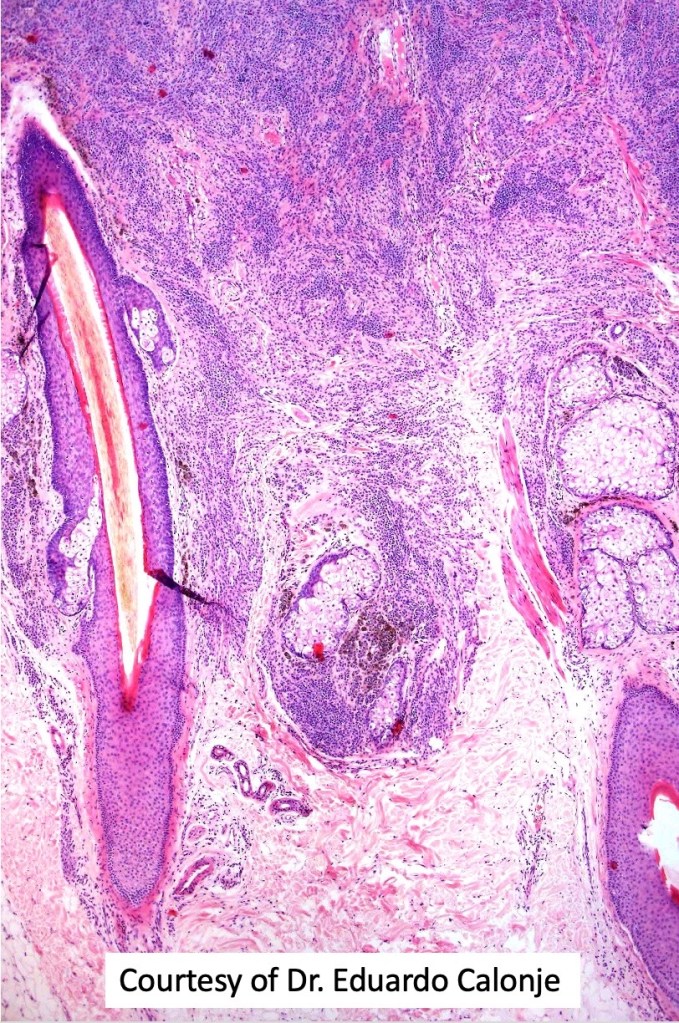

This is uncommon and presents clinically with a history of recent change in color of a common or less often congenital nevus causing concern for melanoma by the clinician. Some, but not all are probably deep penetrating and combined nevus variants. Others may represent follicular type-A cell nests. It is characterized by the presence of deep nest(s) of type -A nevus cells surrounded by & with overlying type-B nevus cells.